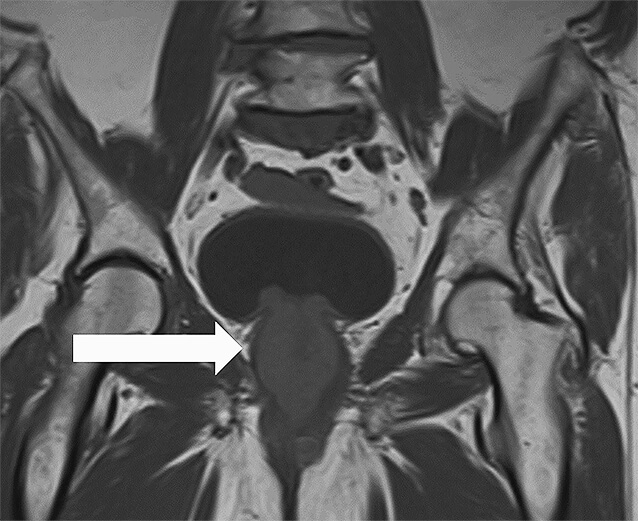

Eine 85-jährige Patientin stellte sich 08/2021 in unserer Klinik wegen einer schmerzlosen Makrohämaturie vor. Zystoskopisch zeigte sich ein Harnröhrentumor, der transurethral reseziert wurde. Histologisch wurde zunächst ein nephrogenes Adenom diagnostiziert. 11/2021 stellte sie sich wegen eines Harnverhalts und lokalen Tumorwachstums erneut bei uns vor. Es erfolgte zur Schonung des Kontinenzmechanismusses nur eine partielle transurethrale Resektion. Histologisch zeigte sich das vorbeschriebene nephrogene Adenom. Aufgrund der in der Literatur für diese Tumorentität beschriebenen hohen Rezidivrate besprachen wir das weitere Procedere in unserem interdisziplinären Tumorboard. Es wurde sich für eine möglichst komplette transurethrale Resektion bei bis dato benigner Erkrankung ausgesprochen. Im Vorfeld erfolgte eine MR-Bildgebung 01/2022 (▶ Abb. 1, 2). Dabei zeigte sich ein ausgedehnter zirkulärer Tumor, der auf der gesamten Länge der Urethra wuchs und den Blasenhals infiltrierte (Tumorausdehnung 4 x 3,3 x 6,6 cm mit deutlichem Kontrastenhancement der Tumormasse). Zudem wurde der Verdacht auf eine lokoregionäre Lymphknotenmetastase an der linken Scheidenwand (2,2 x 1,3 cm) geäußert.